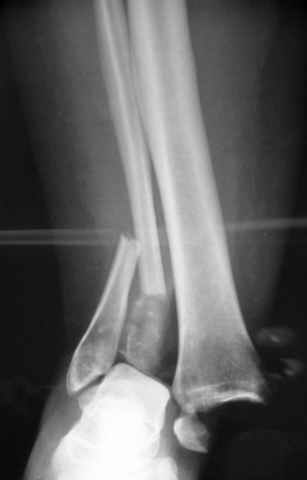

Re: ANKLE FRACTURE

Второй случай сделан из одного разреза

На прямой проекции послеоперационного Рг макроскопически все выглядит очень анатомично, при микроскопическом ( :-)) ) рассмотрении можно все-таки заметить вальгизацию тарана, суставная щель в латеральном отделе сустава несколько уже , чем в медиальном при отсутствии латерального смещения тарана. У меня был аналогичный случай (без LISS , без мини доступа) с вальгусным наклоном тарана при восстановленном ankle mortise при последовательном наблюдении с интервалами в 6-8 недель в послеоперационном периоде отмечалось прогрессирующее сужение суставной щели в латеральном отделе сустава, закончившееся посттравматическим ОА, к счастью боли умеренные, купируемые аналгетиками или своими эндорфинами:-))(активная пациентка, у которой нет времени на болезни....) Какова жизненная ситуация в приведенном вами случае? И последнее, что я хотел бы прояснить для себя - фиксация внутренней лодыжки: я обычно комбинирую фиксацию компрессирующим винтом со спицей - по идее ротационная стабильность должна быть лучше, чем один винт, каковы ваши наблюдения в этом плане?